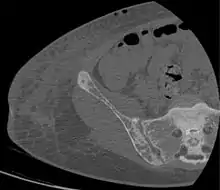

CT shows focal areas of osteosclerosis.[18]

Renal osteodystrophy is usually diagnosed after treatment for end-stage kidney disease begins; however the CKD-MBD starts early in the course of CKD.[1][6] In advanced stages, blood tests will indicate decreased calcium and calcitriol (vitamin D) and increased phosphate, and parathyroid hormone levels. In earlier stages, serum calcium, phosphate levels are normal at the expense of high parathyroid hormone and fibroblast growth factor-23 levels. X-rays will also show bone features of renal osteodystrophy (subperiostic bone resorption, chondrocalcinosis at the knees and pubic symphysis, osteopenia and bone fractures) but may be difficult to differentiate from other conditions. Since the diagnosis of these bone abnormalities cannot be obtained correctly by current clinical, biochemical, and imaging methods (including measurement of bone-mineral density), bone biopsy has been, and still remains, the gold standard analysis for assessing the exact type of renal osteodystrophy.[6][16]